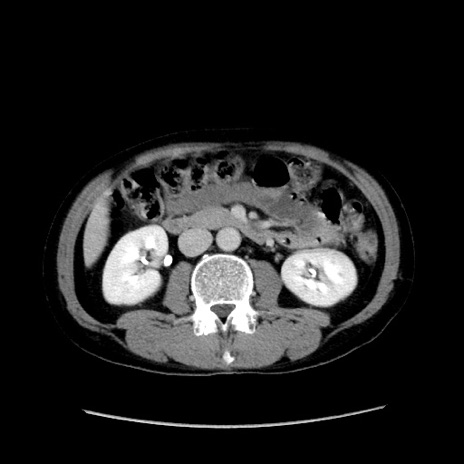

症例37(横断像)

【症例】40歳代 男性

【主訴】腹痛

【現病歴】4時間ほど前に電車に乗車中に臍部上より腹痛出現。徐々に増悪し起立困難となり、救急外来受診。生ものは数日食べていない。今朝お雑煮を食べた。

【身体所見】BT 36.8℃、BP 117/84mmHg、HR 91/min、SpO2 97%、苦悶様、腹部:臍上部広範囲圧痛あり、反跳痛±

【データ】WBC 8100、CRP 0.03